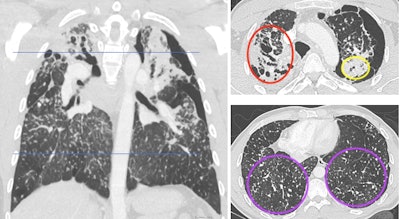

Contrast-enhanced chest CT shows upper predominant fibrosis/lung scarring (red oval), solid masses adjacent to a left-sided pneumothorax (yellow oval) and diffuse silicotic nodules (purple circle). This patient had a history of working in the countertop-cutting industry (15 years), smoking cigarettes (10 pack years), and active tuberculosis (treated 7 years prior and excluded at the time of this image with laboratory testing). Image courtesy of the RSNA.

The team classified CT images as typical or atypical for chronic silicosis. Markers for atypical findings included mediastinal lymphadenopathy and upper-lobe predominant small nodularity and/or progressive massive fibrosis. All 21 patients were symptomatic, with the most common symptoms being dyspnea (n = 19) and cough (n = 17).

On secondary retrospective review, the team found that 11 cases were typical for silicosis, while the other 10 cases had atypical imaging features. Pulmonary function tests meanwhile showed a restrictive pattern in 18 cases.

Also, patients with consolidations had lower diffusing capacity for carbon monoxide (DLCO) test scores than patients without large opacities (18.1 vs. 24.5, p = 0.02).